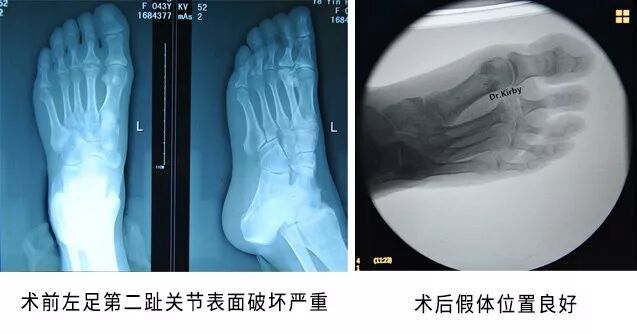

患者葉女士,半年前在走路時(shí)間久后感到左足第二趾疼痛,休息后稍有好轉(zhuǎn),但左足第二趾會(huì)有腫脹現(xiàn)象,曾在多家醫(yī)院對(duì)癥治療,均未見明顯好轉(zhuǎn)。

經(jīng)人介紹,葉女士找到了省級(jí)知名骨科專家、邦爾骨科集團(tuán)首席專家、嘉興邦爾骨科醫(yī)院院長(zhǎng)趙凱教授。經(jīng)過檢查,診斷為“左足第二跖趾關(guān)節(jié)炎”,而且關(guān)節(jié)面粗糙,破壞嚴(yán)重,之后為患者進(jìn)行了“左側(cè)人工第二跖趾關(guān)節(jié)置換術(shù)”。

術(shù)后患者足趾功能活動(dòng)改善,恢復(fù)良好。

術(shù)前術(shù)后對(duì)比圖